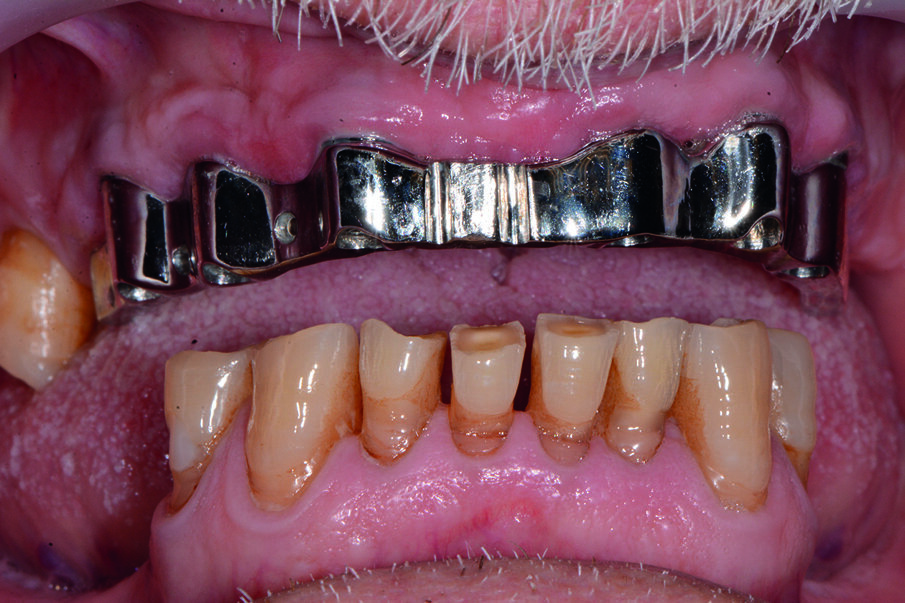

Condividiamo con il paziente la scelta terapeutica di riabilitazione implantoprotesica che nella 1 fase consisterà in riabilitazione occlusale mediante l’applicazione di protesi provvisoria, e successivamente inserimento di 6 impianti nel mascellare a carico ritardato e seguente applicazione di barra per una overdenture. Il paziente necessita di una riabilitazione oro-implantare protesica, in quanto sia all’esame obiettivo che all’esame radiografico presenta una ridotta dimensione verticale che negli anni ha portato alla distruzione degli elementi inferiori dal 34 al 44, e persistenza di 11, 13, 17, 25 che presentano abrasioni e abfrazioni sulla superficie coronale (Fig. 2). Dopo aver condiviso con il paziente le problematiche terapeutiche dovute anche alla sua condizione di patologia sistemica, si decise, di procedere con avulsione dei denti dell’arcata superiore e contestuale inserzione di 6 impianti, per un una riabilitazione implantoprotesica overdenture su barra, a carico ritardato a 6 mesi.

La tecnica chirurgica scelta permetterà di ridurre la durata dell’intervento e il rischio operatorio: sanguinamento, calo di glicemia, rischio di infezioni. È stato utilizzato un anestetico con una bassa concentrazione di adrenalina al fine di evitare un effetto iperglicemizzante ed è stata eseguita una terapia preventiva della sepsi per evitare qualsiasi rischio al paziente diabetico (Figg. 3a, 3b).

Dopo la terapia chirurgica, si inserisce una protesi totale provvisoria, che il paziente porterà per 6 mesi (Fig. 4b). Dopo i 6 mesi si monta la barra e la protesi totale superiore (Figg. 5, 6), che oltre a migliorare la masticazione e la fonetica del paziente, supporterà anche i tessuti molli, labbro, guancia, ridando al paziente un aspetto del sorriso giovanile e un supporto dei tessuti molli orali delle labbra, delle guance e delle rughe geniene (Figg. 7, 8). Il paziente viene inserito in un piano di mantenimento con un follow-up ogni 3 mesi (Fig. 9).